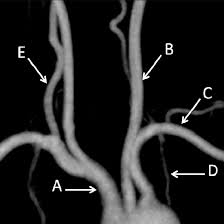

Medifyhome has collaborated with the best pathology laboratories that are NABL and NABH certified and follow ISO safety guidelines to provide the best MR Angiography Aortic Arch at an affordable price for needy individuals. The aortic arch is a structure that belongs to the largest artery in the body, the aorta, and has a critical function of delivering oxygenated blood from the heart to the head, all the organs suspended in the abdominal cavity and the upper limbs. From it springs major branches that provide blood to the brain, neck as well as the arm. As the aortic arch is a critical part of the cardiovascular system, any pathological conditions, including aneurysms, stenosis or dissections concern the subject’s health state.

Magnetic Resonance Angiography is an invasive but highly specialized technique of X-ray that uses magnetic fields and radio signals to map arteries including the aortic arch. It provides the means for immediate visualisation and assessment of the aorta and its branches with great anatomic accuracy, which otherwise would have required catheterisation of the patient.It is advantageous in this imaging technique because imaging is done using MRI and not radionuclide which is a safety boost to patient’s who require frequent imaging. MR Angiography is also most beneficial in the patient’s high risk factors such as family history of aortic disease or connective tissue diseases for example. To schedule an appointment for MR Angiography Aortic Arch, simply contact Medifyhome or call our customer care at +919100907036 or +919100907622 for more details and queries.